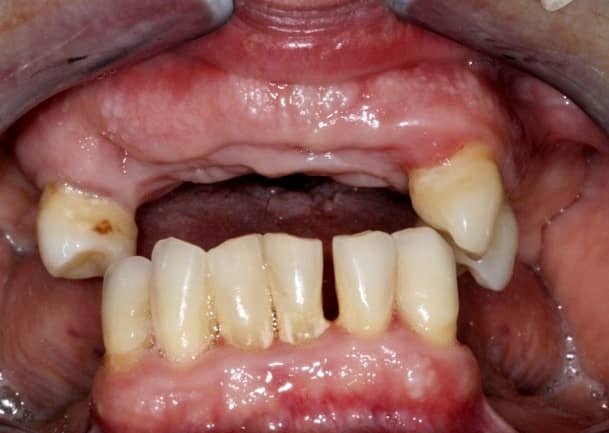

Hölgypáciensünk azzal a panasszal érkezett dr. Sápi Béla kollégánkhoz, hogy pár hónapja több fogát is el kellett távolítani, és azóta sem funkcionálisan, sem esztétikailag nincs kibékülve fogai állapotával.

kapcsos részleges lemezes fogpótlás előtt